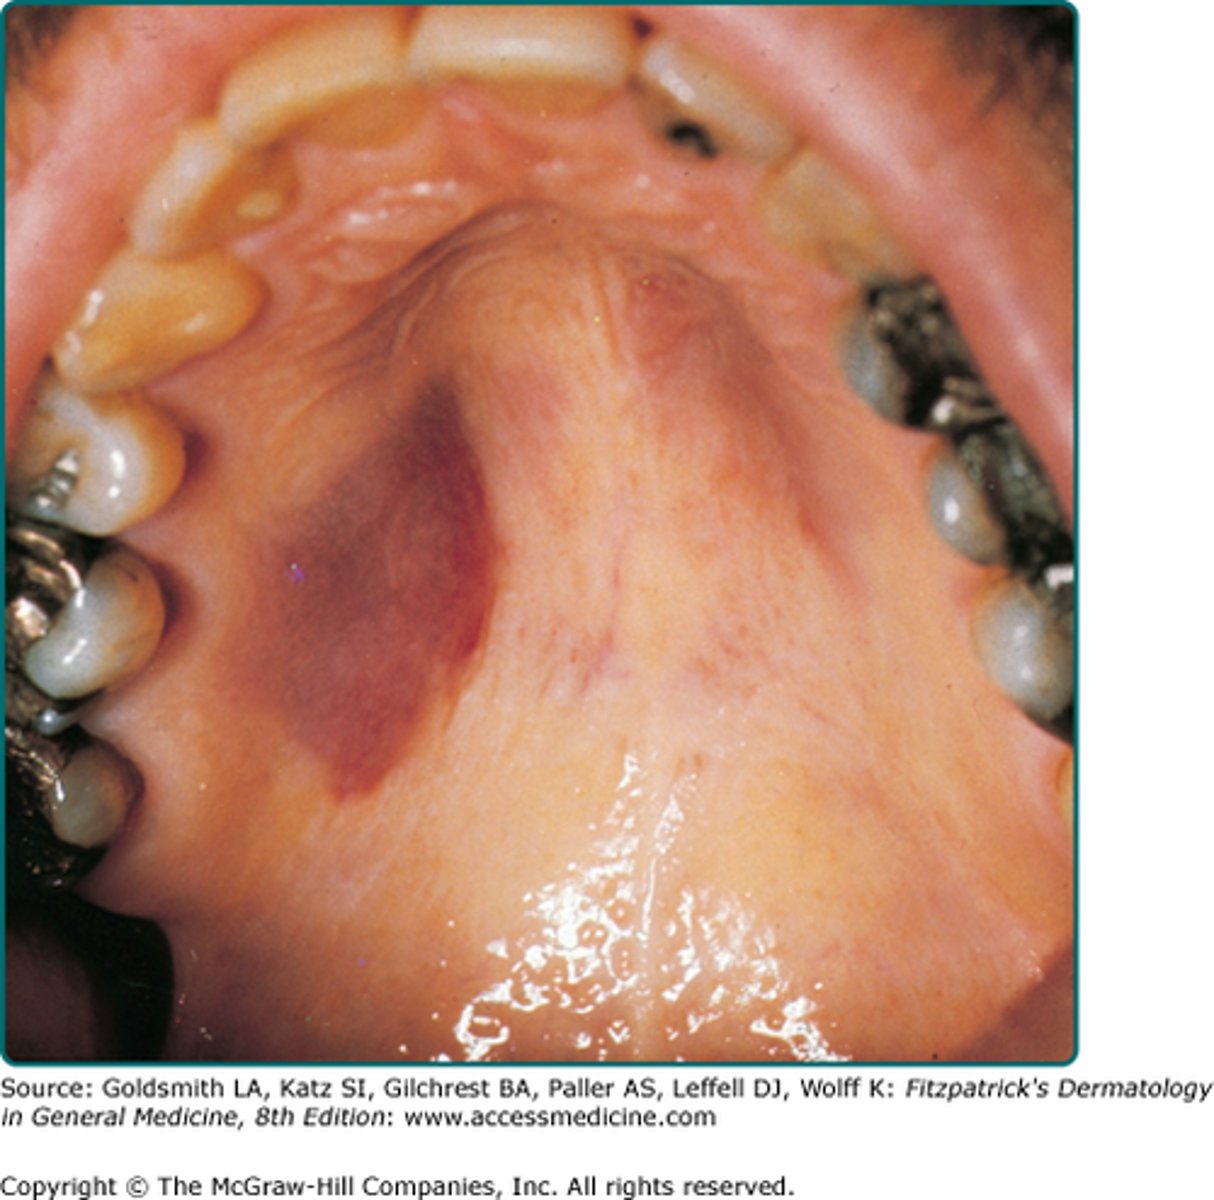

Adult patient with purple lesions on palate and said they had similar lesions on their body too. What is the most probable cause?

- Surge Weber

- Erthyema Multiforme

- HIV

- Malignant Melanoma

HIV

- lesions are Kaposi sarcoma